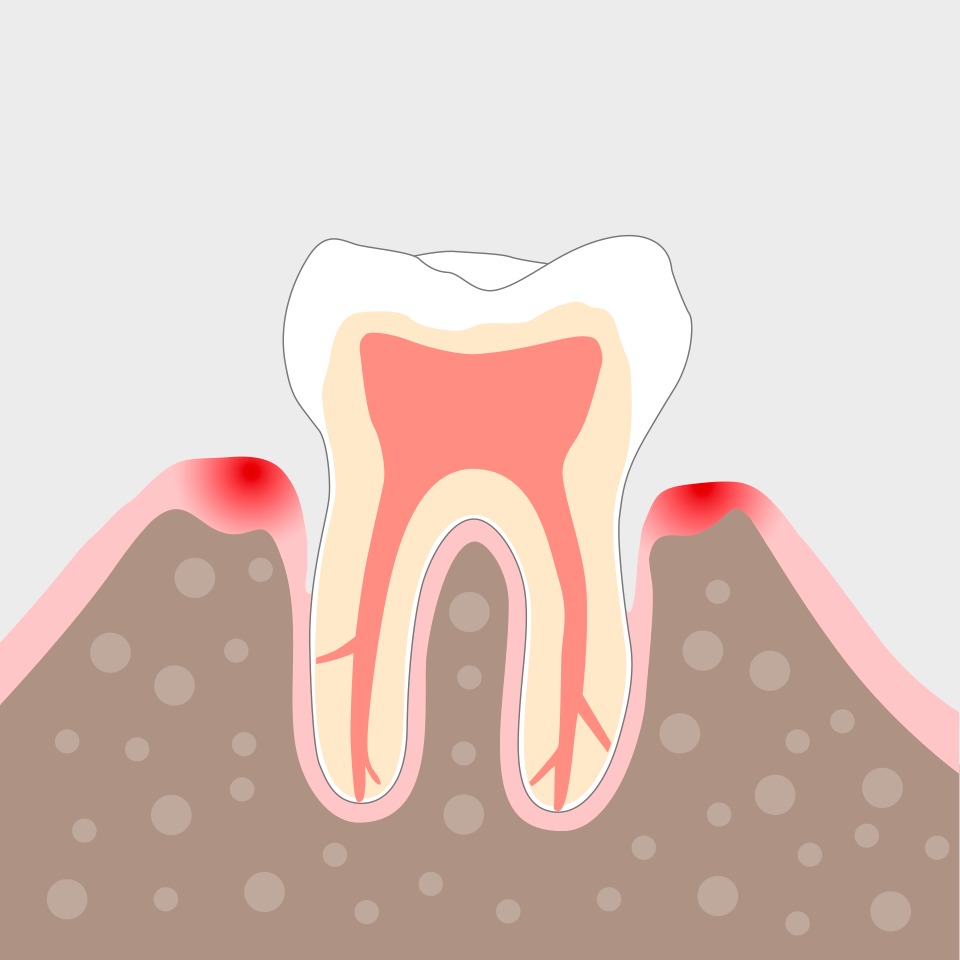

Nach wenigen Wochen ist die Entzündung zum Stillstand gekommen und das Zahnfleisch beginnt, sich zu regenerieren.

Die Behandlung zeigt schon bald erste Erfolge: Das Zahnfleisch wird wieder fest und rosig, das Zahnfleisch legt sich enger an den Zahn und die vertieften Taschen bilden sich zurück.